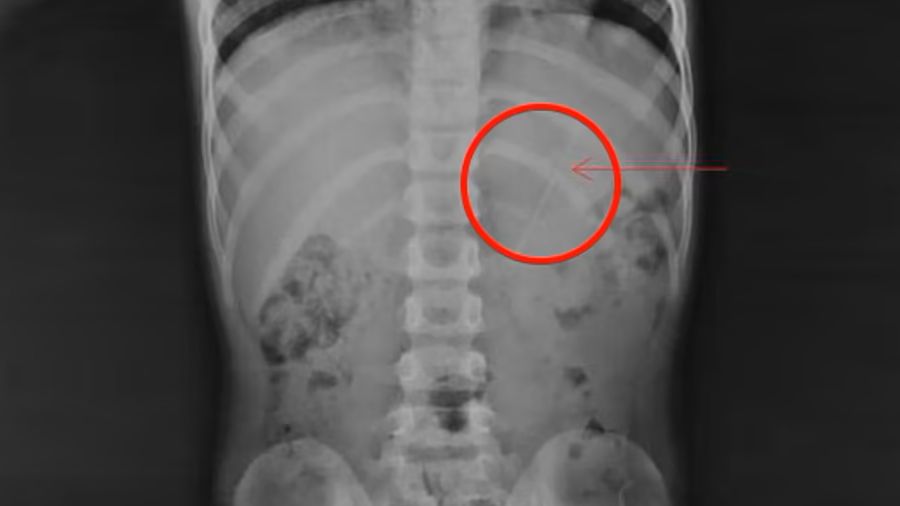

W szpitalu siedmiolatka poddano prześwietleniu, które wykazało ołówek znajdujący się w jego żołądku. Wszystkie organy chłopca funkcjonowały prawidłowo. Zatrzymano go w klinice na obserwacji, gdzie przez osiem godzin mógł tylko pić wodę i zjeść banana. Następnie wykonano kolejne badanie.

Na rentgenie lekarze zobaczyli wówczas, że ołówek przesunął się do zastawki krętniczo-kątniczej, które stanowi przejście z jelita cienkiego do grubego.